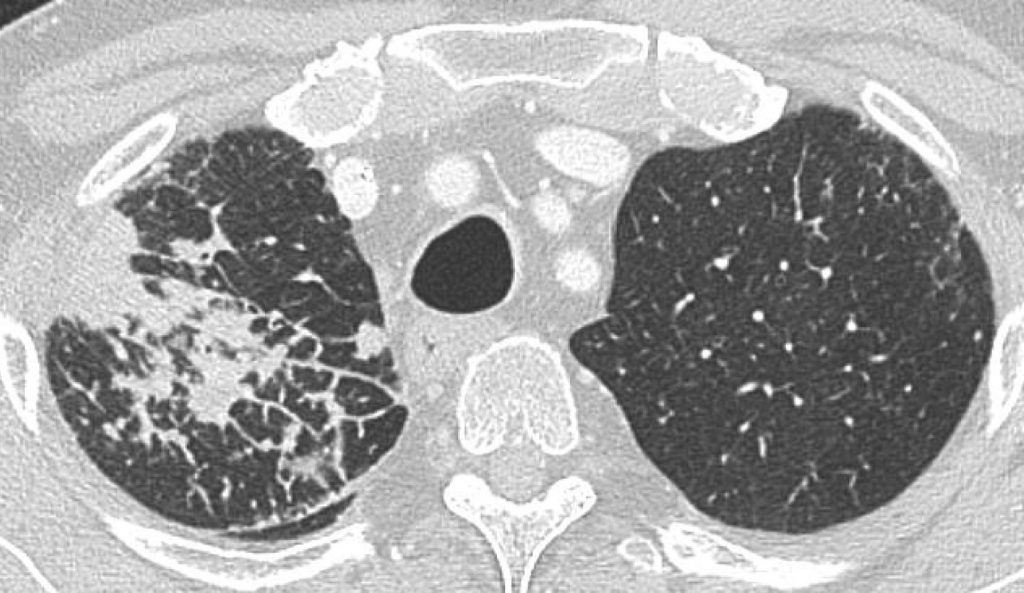

La lymphangite carcinomateuse associe un épaississement des parois bronchiques, des lignes septales irrégulières (correspondant à la dilatation des vaisseaux lymphatiques) et une micronodulation de distribution périlymphatique (figure 101.7).

Fig. 101.7. Scanner thoracique.

L’apex pulmonaire droit est le siège de lignes septales associées à des nodules de taille variable de topographie sous-pleurale et périlymphatique. Il s’agissait d’une lymphangite carcinomateuse compliquant un adénocarcinome bronchique multifocal du poumon droit.

Source : CERF, CNEBMN, 2022.